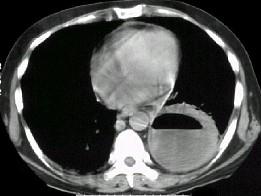

问题 男,36岁,胸痛半月伴发高热,胸片发现占位性病变,CT检查如图,最可能的诊断为 ( )

选项 A、左下肺囊肿 B、左下肺肺炎 C、左下肺癌并空洞形成 D、左侧胸腔积脓 E、左下肺肺脓肿

答案 E